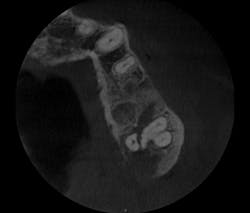

I prescribed a CBCT scan to evaluate site No. 14 prior to implant placement and to evaluate tooth No. 15. After capturing a CBCT scan on the CS 9300 (with a 5 cm x 5 cm field of view and a resolution of 90 ÎĽm), the image clearly showed a palatal root fracture on tooth No. 15 across from the cross-sectional and axial scan views (figs. 1, 2). Thanks to the enhanced diagnostic quality of the images, we decided to extract the tooth.

Figure 2: